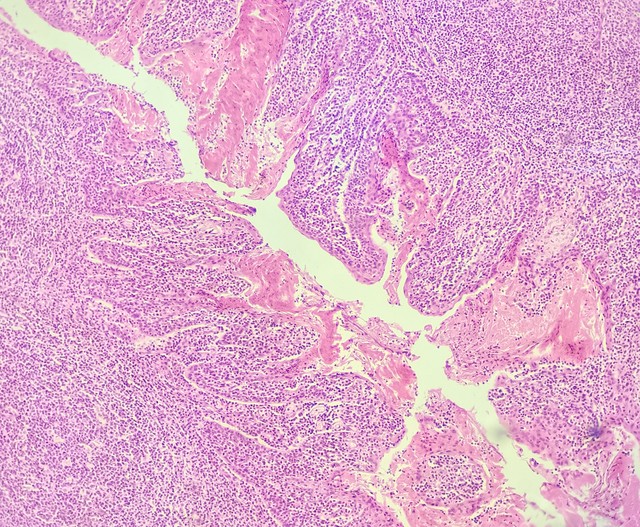

The definition of stage IIB cervical cancer is "the tumor invades the upper two-thirds of the vagina, or extends to the pelvic sidewall, but has not involved the bladder or rectum," like "vines have reached key pelvic areas but have not rooted into the viscera":